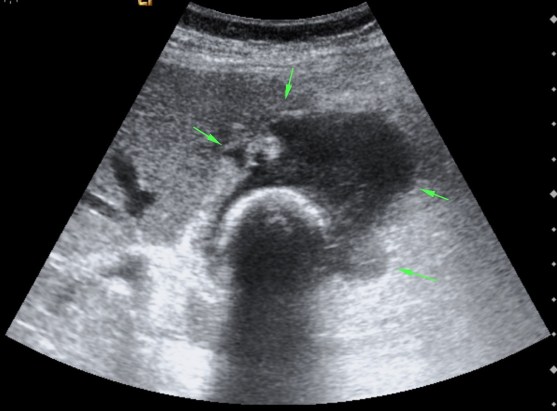

Se realiza ecografía abdominal:

Con estos hallazgos ecográficos podemos concluir que el paciente presenta una COLECISTITIS AGUDA.

Criterios ecográficos de colecistitis (No existe consenso generalizado):

– Murphy ecográfico positivo y colelitiasis: es la combinación de signos ecográficos más predictiva de colecistitis aguda (VPP 92%). Puede resultar difícil observa la litiasis si ésta se localiza en el conducto cístico o en el cuello de la vesícula. Con engrosamiento mural el VPP aumenta al 94%)

– Otros signos secundarios son:

- Engrosamiento de la pared vesicular (>4mm) en ausencia de enfermedad hepática crónica, ascitis o insuficiencia cardiaca (el VPP asciende al 94%).

- Líquido perivesicular.

- Imágen de triple pared con capa hipoecoica central.

- Vesícula biliar distendida.

- Presencia de barro o material ecogénico en el interior de la vesícula.